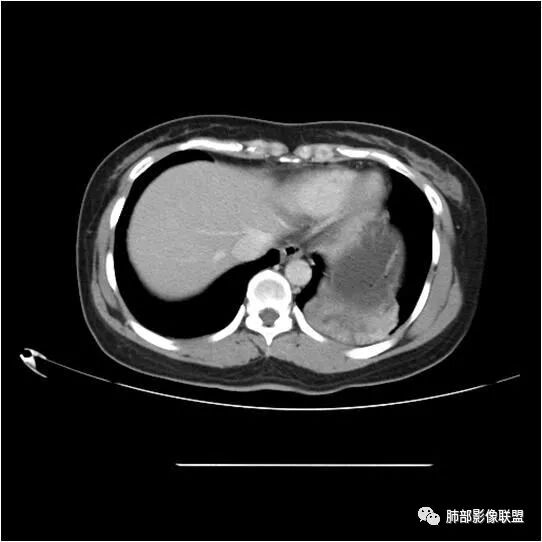

下面看第三部分了,3月20日补增强扫描:

M-Imaging :错了,这么大,膈肌后方南边:定位?定性?Shelia:肺外。感觉病灶是个扁平状,虽然没有蛇纹血管征,但是延迟强化,怀疑纤维来源,考虑sft

M-Imaging :肿块与胸膜夹角是锐角,有分叶,觉得肺内Lotus:mpr重建再看一下南边:与支气管有关系吗Shelia:没有关系。与胸膜分不清

南边:

宇宙星空:没有关系。长轴与胸膜平行吧?

Coke with ice:与肺韧带有关系。与肺韧带的夹角呈钝角,感觉有胸膜尾

宇宙星空:糊墙关系:

南边:边缘这么光滑,无分叶,与胸膜关系密切

D字征

首先良性,倾向于SFT,不除外PSP

小微:肺外肿瘤

宇宙星空:延迟明显强化,其内可见条索状低密度,支持SFT

lmg:其内可见血管穿行吧,考虑SFT

一米阳光:与膈胸膜关系密切,肺受压。考虑SFT

远方: